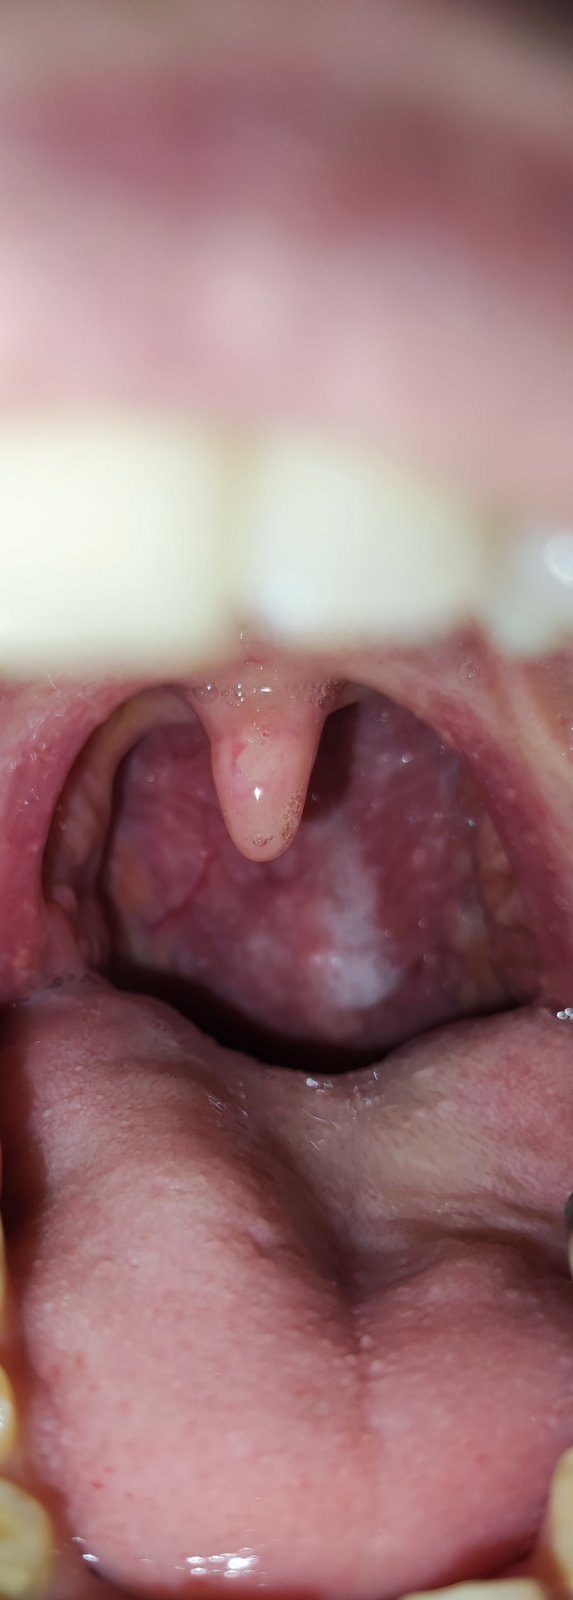

Biele fľaky v hrdle: Čo znamenajú?

Prosím vás čo sú tie biele fľaky vzadu? Je to zapálené hrdlo ?

Angina?